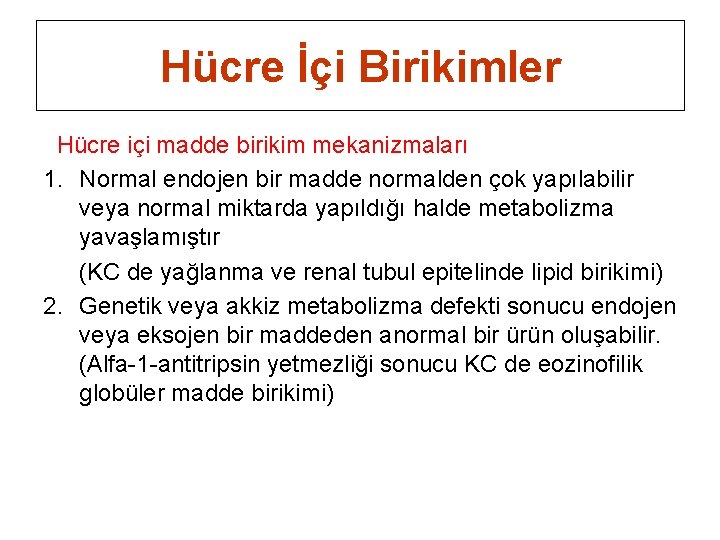

Hücre İçi Birikimler Hücre içi madde birikim mekanizmaları 1. Normal endojen bir madde normalden çok yapılabilir veya normal miktarda yapıldığı halde metabolizma yavaşlamıştır (KC de yağlanma ve renal tubul epitelinde lipid birikimi) 2. Genetik veya akkiz metabolizma defekti sonucu endojen veya eksojen bir maddeden anormal bir ürün oluşabilir. (Alfa-1 -antitripsin yetmezliği sonucu KC de eozinofilik globüler madde birikimi)